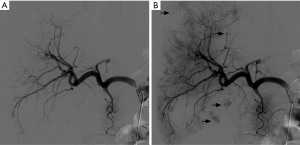

Angiographic lesion vascular grade assessment

Visual vascular grading of the lesions was performed using images obtained during diagnostic angiography. For each patient, two board-certified interventional radiologists blinded to the treatment regimen reviewed the digital subtraction angiograms. Angiographic tumor vascularity was categorized into 4 grades for each patient. We conducted our visual rating inspired by rating systems used in a study focusing on recurrent glioblastoma multiforme and anaplastic astrocytomas (10), another study utilizing digital subtraction angiography (DSA) for visual rating in gliomas (11), and research on the vascularization of liver metastases (12). The angiographic tumor vascularity of each patient was classified as follows: grade 1, avascular tumors; grade 2, mild tumor flushing; grade 3, tumor flushing with an arterial network; and grade 4, abnormal vascularization and arteriovenous shunting (Figures 1-4). Compared with the reference study (12), the lesions of patients with grade 1 and 2 tumors in our study showed similar or less contrast enhancement than the normal parenchyma, aligning with the hypovascular class in the reference. In contrast, the lesions of patients with grade 3 and 4 tumors, which exhibited a higher contrast than the surrounding hepatic parenchyma, corresponded to the hypervascular class in the reference study.